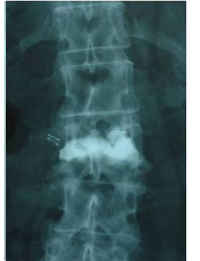

Pre- and post-operative comparison of a cemented kyphoplasty

Female, age 55, compression fracture of L2

Before 2

after 2